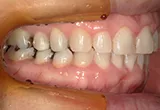

| 年齢/性別 | 40代女性 |

| 主訴 | 右上の詰め物が取れた |

| 治療内容 | 歯周病とむし歯の治療を目的に来院。左下の奥歯は根の状態が悪く、病変も大きかったため保存が困難と判断。 インプラント治療を実施しました。 |

| 治療期間 | 4か月 |

| 費用 | 566,500円税込 |

| リスク・副作用 | 炎症反応によって術後に腫れが生じることがあります。その程度は、手術の範囲や方法によって異なりますが、多くの場合、時間の経過とともに徐々に治まります。 ごく稀に、下顎奥歯の外科手術後に、唇や顎に痺れを感じることがあります。 |